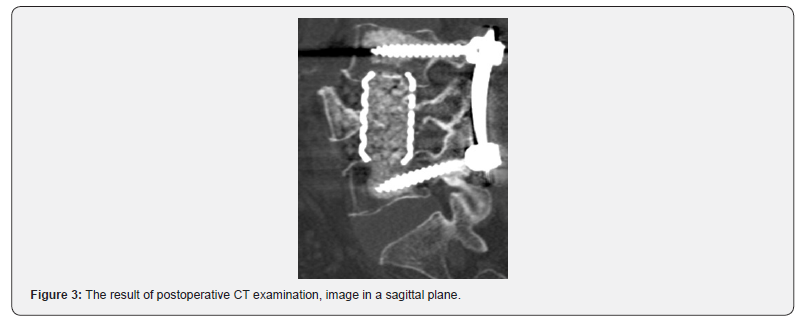

A considerable axial pain relief was evaluated in 21 case, no cases with pain intensity over 4 (VAS) and ODI over 40% were detected. No resorption of material used for screw augmentation was detected during the follow-up period, augmented parts of vertebrae remained hyperdense. Application of the suggested technique can be demonstrated by a clinical case. The patient was treated because of osteoporotic OF4 fracture of L4 vertebra. The calculated radiodensity came to 65 HU, the T criterion by DXA value accounted for -3,5. Patient underwent L3-L4-L5 pedicle screw fixation with suggested technique of augmentation. As only axial pain was present and no neurological symptoms were detected nerve root decompression was not performed. Preoperative results of CT examination are present in (Figures 1 & 2). Postoperative CT images and results of CT examination 18 months after are presented in (figures 3- 6) respectively.